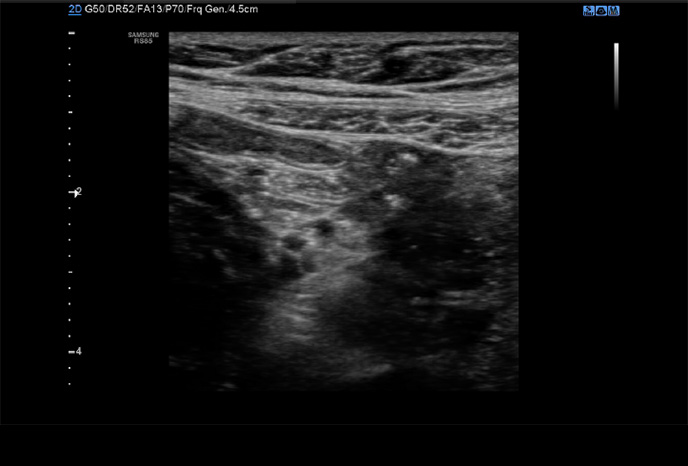

S-Detect™ for Thyroid

Poloautomatický nástroj pro hodnocení štítné žlázy

Nástroj, který analyzuje vybrané léze v ultrazvukovém vyšetření štítné žlázy a poskytuje analytická data. Poskytuje standardizovaný report založený na normách *ATA, BTA, EU-TIRADS, K-TIRADS and ACR TI-RADS a pomáhá tím zrychlit a zjednodušit pracovní postup